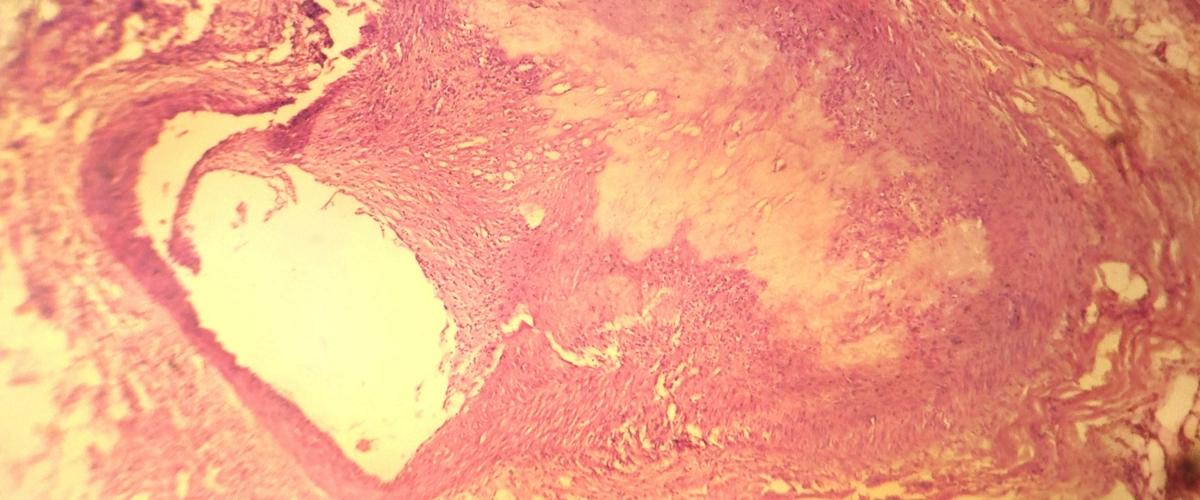

Беспокойный сон был четко связан с более высокими концентрациями воспалительных биомаркеров, включая моноциты и нейтрофилы, которые играют ключевую роль в развитии атеросклероза.

Эти данные согласуются с результатами предыдущих исследований на моделях мышей, поясняют авторы. Тогда в экспериментах было показано, что прерывание сна у грызунов вызывало более высокие концентрации этих показателей и способствовало развитию атеросклеротических бляшек.

Атеросклероз часто начинает развиваться еще в молодом возрасте, но протекает незаметно и может быть обнаружен уже в критический момент, когда атеросклеротические бляшки блокируют кровоток и приводят к инсульту и инфаркту. Это важный довод в пользу того, чтобы следить за качеством и продолжительностью сна, подчеркивают ученые. Однако этот аргумент не единственный.